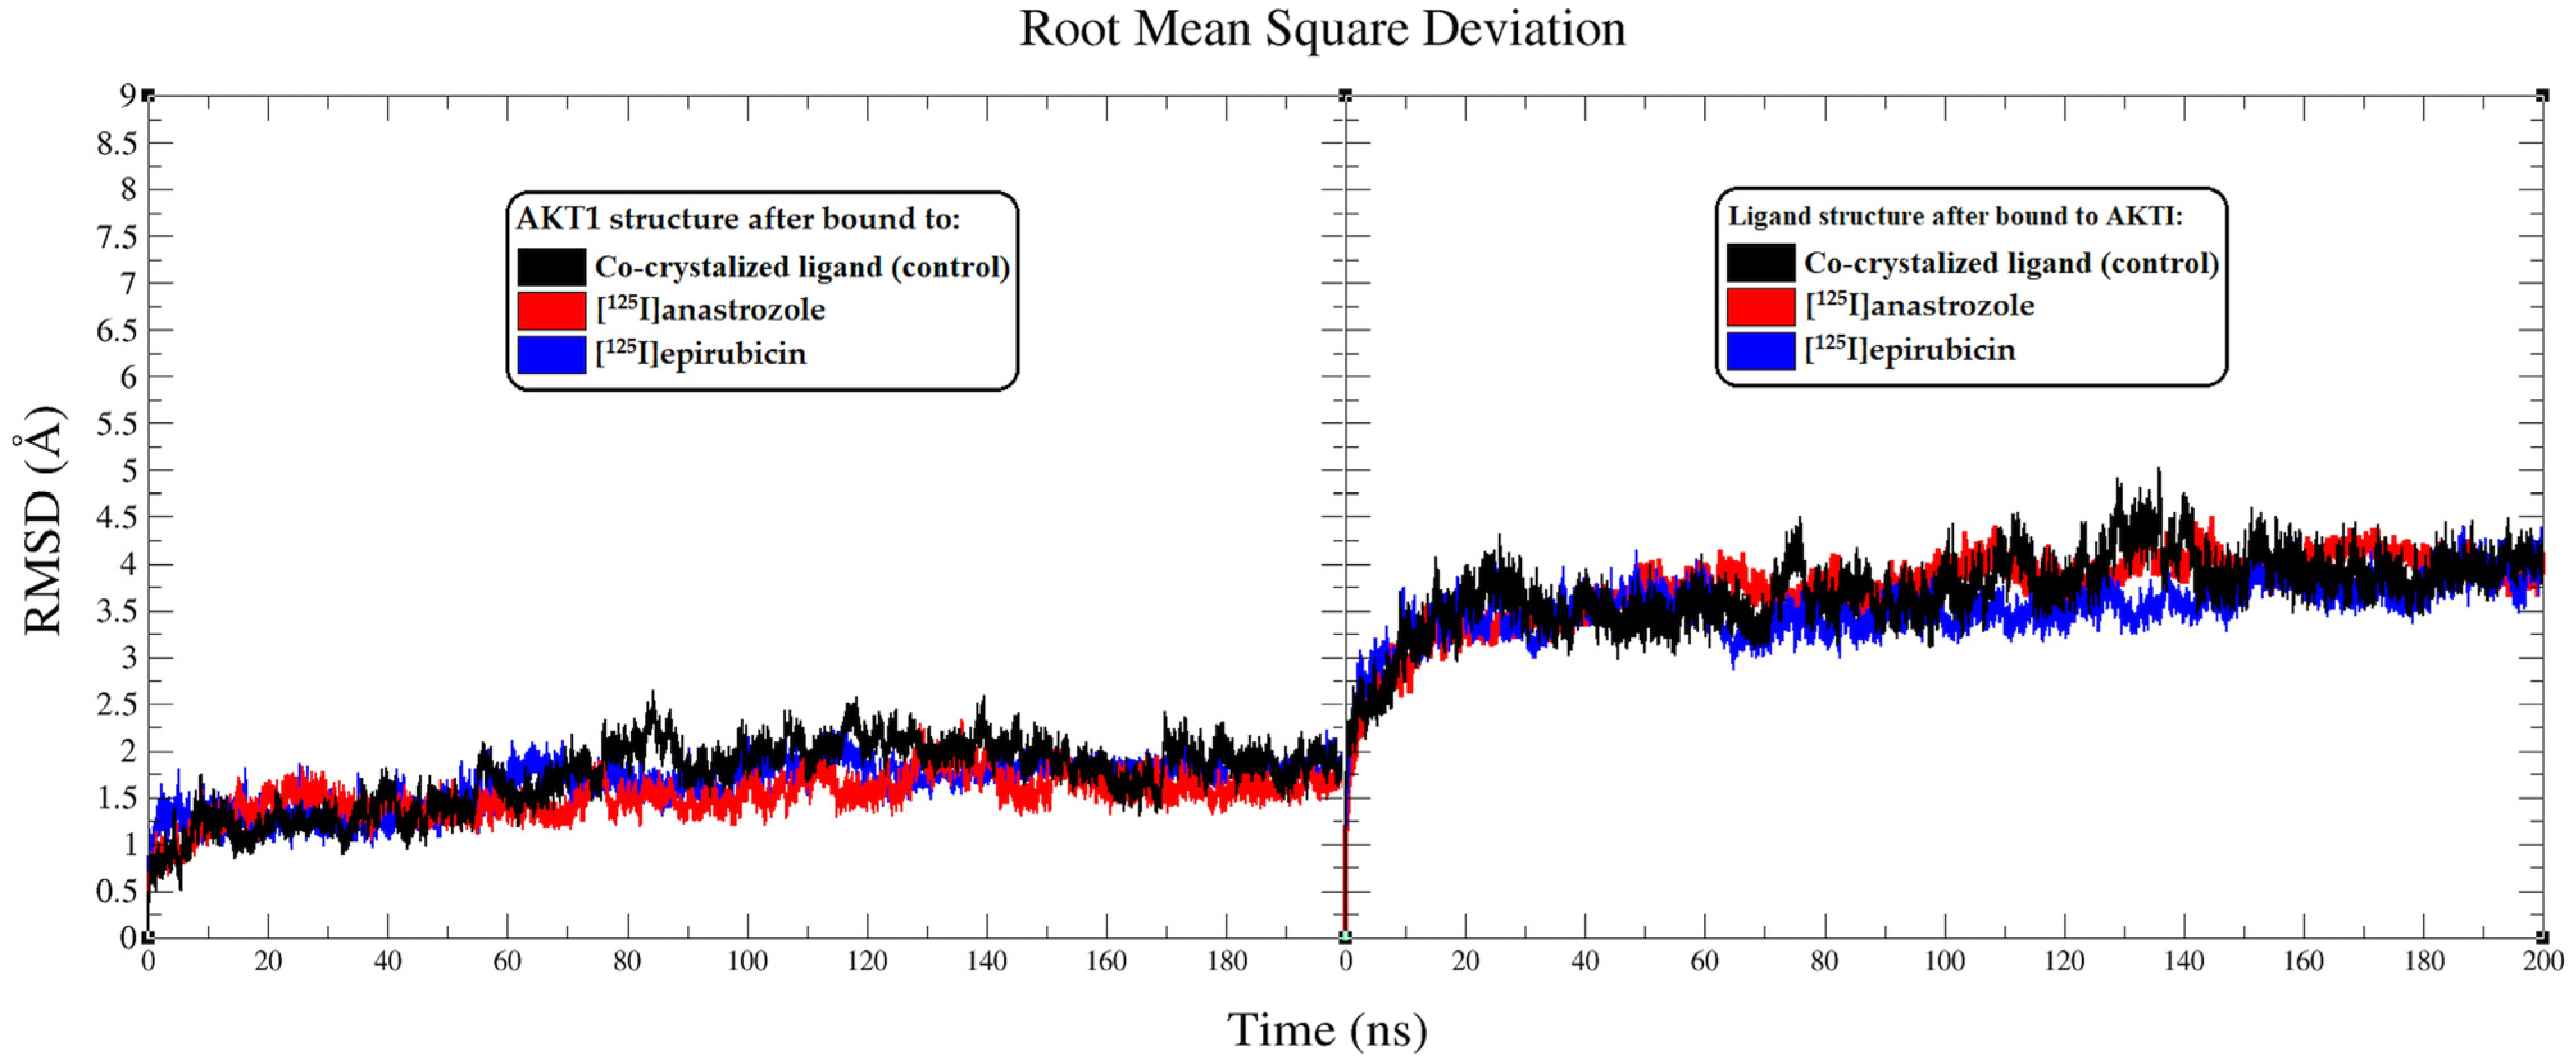

2.2. Molecular Dynamic Simulation

3.2. Molecular Dynamic Simulation

| System | ΔGbind (kcal/mol) | Electrostatic (kcal/mol) | Van der Waal (kcal/mol) | Polar Salvation (kcal/mol) | Non-Polar Salvation (kcal/mol) |

|---|---|---|---|---|---|

| AKT1-Co-crystallized ligand | −16.38 ± 0.14 | −11.28 ± 0.11 | −13.52 ± 0.12 | 19.11 ± 0.12 | −10.69 ± 0.13 |

| AKT1-[125I]anastrozole | −20.03 ± 0.15 | −12.86 ± 0.13 | −14.69 ± 0.11 | 19.84 ± 0.13 | −12.32 ± 0.12 |

| AKT1-[125I]epirubicin | −23.57 ± 0.14 | −14.73 ± 0.12 | −15.84 ± 0.14 | 19.86 ± 0.12 | −12.86 ± 0.13 |